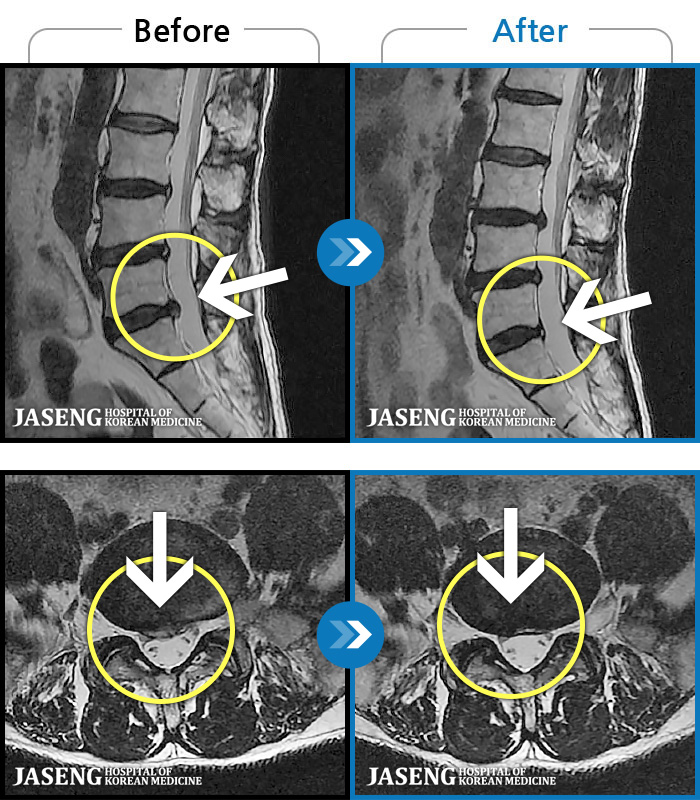

1,257 MRI ũ ʸ Ȯϼ.